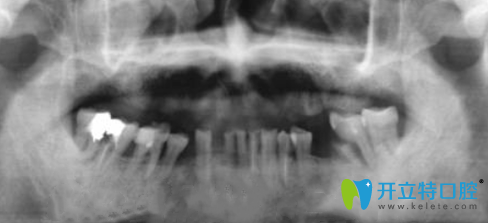

金臺口腔為張叔拍完X光圖片:

那么,種植牙即拔即種好不好呢?田院長采用數(shù)字化3D技術(shù),一站式完成牙齒種植流程,不切開、創(chuàng)口小、無需縫合降低腫脹疼痛與不適感。術(shù)后6個(gè)月后牙槽骨和種植體緊密結(jié)合,然后再安裝牙冠。